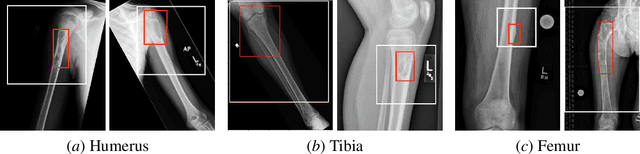

Abstract:Insufficient training data and severe class imbalance are often limiting factors when developing machine learning models for the classification of rare diseases. In this work, we address the problem of classifying bone lesions from X-ray images by increasing the small number of positive samples in the training set. We propose a generative data augmentation approach based on a cycle-consistent generative adversarial network that synthesizes bone lesions on images without pathology. We pose the generative task as an image-patch translation problem that we optimize specifically for distinct bones (humerus, tibia, femur). In experimental results, we confirm that the described method mitigates the class imbalance problem in the binary classification task of bone lesion detection. We show that the augmented training sets enable the training of superior classifiers achieving better performance on a held-out test set. Additionally, we demonstrate the feasibility of transfer learning and apply a generative model that was trained on one body part to another.